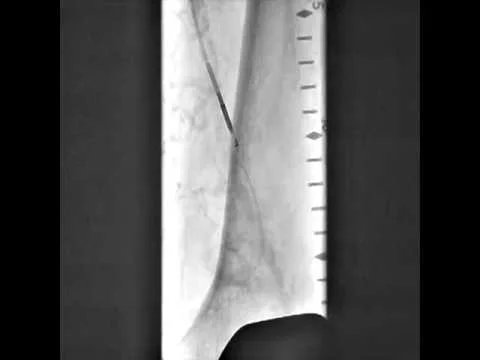

Viance SFA CTO Cross #1